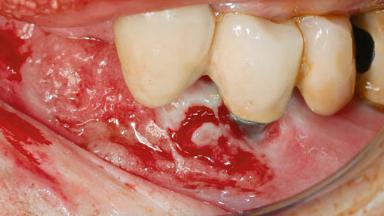

Peri-implant Carcinoma

Oral implants are highly successful and offer long-term benefits, especially in the rehabilitation of edentulous patients or patients with oral defects following ablative tumor surgery (Albrektsson and coworkers 1986), and also after radiation therapy (Schiegnitz and coworkers 2014). With the number of implants placed globally going into the millions, implant dentists have observed some rare adverse events. Although carcinogenesis around implants is an exceedingly rare phenomenon, we recently reported about 15 patients treated for carcinomas adjacent to implants at our clinical department over a period of fifteen years (Moergel and coworkers 2014). The following case represents a patient of this cohort; it discusses possible risk factors and makes suggestions for a recall schedule. A 70-year-old woman was referred to our outpatient department for evaluation of a rapidly growing macroscopic alteration of the mucosa in the left mandible.